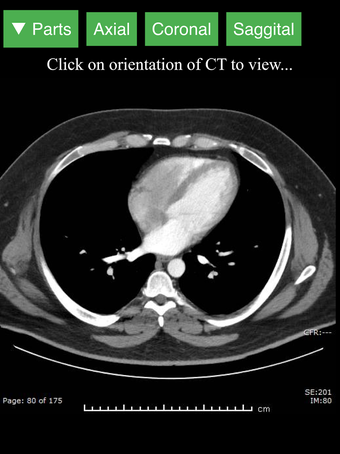

Radyoloji BT Görüntüleyicisi, doktorlar, tıp öğrencileri, radyoloji teknisyenleri ve diğer sağlık profesyonellerinin insan vücudu ve anatomisi hakkında daha fazla bilgi edinmelerine yardımcı olan faydalı bir araçtır. Uygulama, en önemli insan vücut parçalarının detaylı kesit çizimlerini içerir. Ayrıca, anatomiyi daha iyi görmek için görüntü etrafında döndürme, yakınlaştırma ve kamera hareket ettirme imkanı sunan etkileşimli bir 3D model içerir.

İnsan vücudu hakkında daha fazla bilgi edinmenize yardımcı olacak bir araç arıyorsanız, Radyoloji BT Görüntüleyicisi harika bir seçimdir. Detaylı çizimler ve etkileşimli bir 3D model içerir.